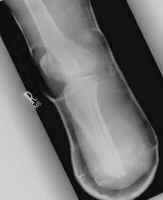

Immediate post-operative films of a good BKA. Stump-shrinking cast and skin staples